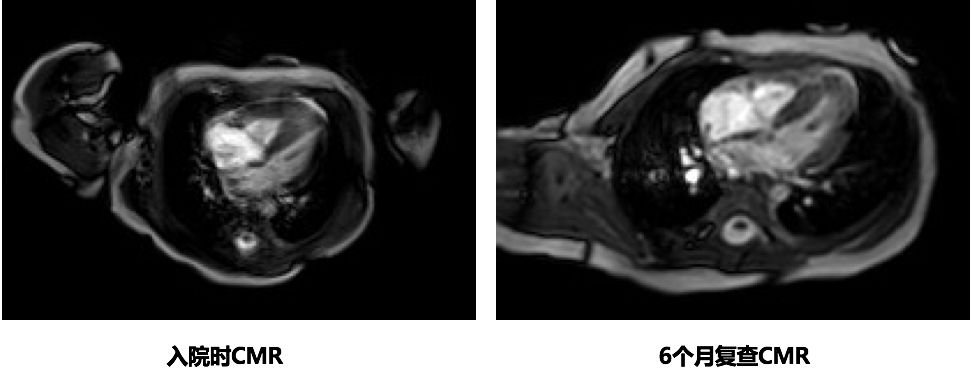

6个月复查CMR

入院时CMR可见右室明显增厚,经积极治疗,6个月复查右室心肌厚度基本恢复正常